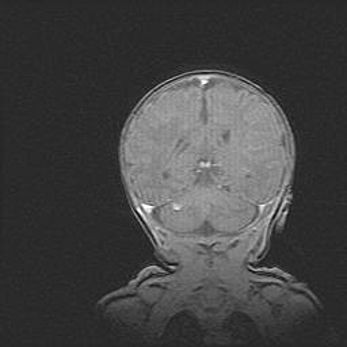

Церебральная ишемия II.

Возраст: 5 дней

Вес: 3400 г

Пол: женский

Окружность головы: 35 см

Срок гестации: 39 недель

Церебральная ишемия – это заболевание, характеризующееся недостаточностью (гипоксией) либо полным прекращением (аноксией) снабжения мозга кислородом по причине закупорки одного или нескольких сосудов. Это приводит к  что метаболическим расстройствам различной степени тяжести в тканях головного мозга, развитию коагуляционных некрозов и гибели нейронов.